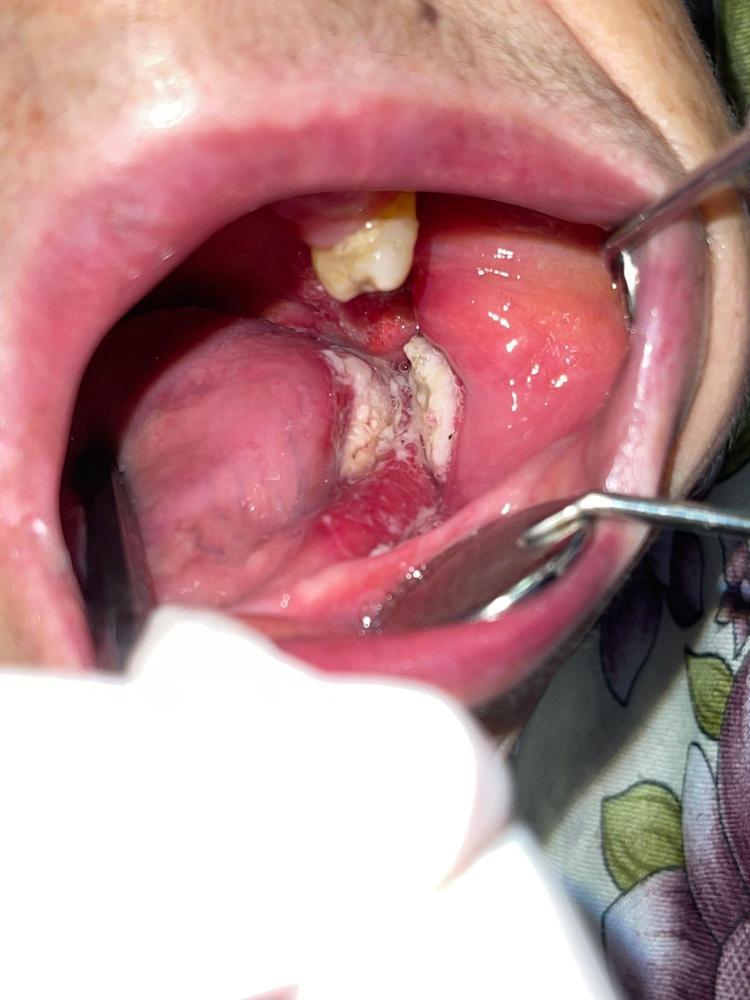

Ağız kanserinde erken tanı gerçekleşirse hastaların ölümle sonuçlanmasının önüne geçilebileceğini ifade eden Prof. Dr. Gündüz, “Biz kurum olarak Karadeniz'in en büyük üniversitesiyiz ve de fakülte olarak da Karadeniz'de büyük bir hizmet vermekteyiz. Ortalama yaklaşık günde 500 hasta, aylıkta 10 bine yakın hasta bakıyoruz. Biz yapmış olduğumuz seminerlerde hem öğrencilerimizi hem asistanlarımızı hem de halkımızı bu konuda bilgilendirmeye çalışıyoruz. Erken tanı eğer gerçekleşirse bu hastalıkların ölümle sonuçlanmasının nispeten önüne geçmiş oluyoruz. Çünkü erken tanı biliyorsunuz her kanser vakasında çok önemli bir yer tutmakta. Herhangi birisi ağzında eğer 2 haftanın üzerine geçmeyen bir yara varsa mutlaka en yakın diş hekimine başvurması gerekmekte. Sebepsiz yere dişlerin sallanması, uyuşukluk olması, yüzde sebepsiz ağrıların, çene bölgesinde sebepsiz ağrıların oluşması kanserlerin başlangıç bulguları arasındadır. Zaten kanserlerin en fazla oluştuğu yerler ağız içerisinde dilin özellikle arka kenarlarıdır. Bunlar ne yazık ki başlangıçları da ağrısız olduğu için bir kısmının gözden kaçabilmekte. O yüzden insanlarımızdan, halkımızdan bu konuda dikkat etmeleri, eğer böyle bir lezyonla muhatap olurlarsa mesela bir yakınından ağız içerisindeki görüntüsünü çekmesini talep etmeli. 2 hafta sonra da aynı şekilde bu görüntü duruyorsa veya daha da büyümüşse en yakın merkeze gitmesini önermekteyiz” ifadelerini kullandı.